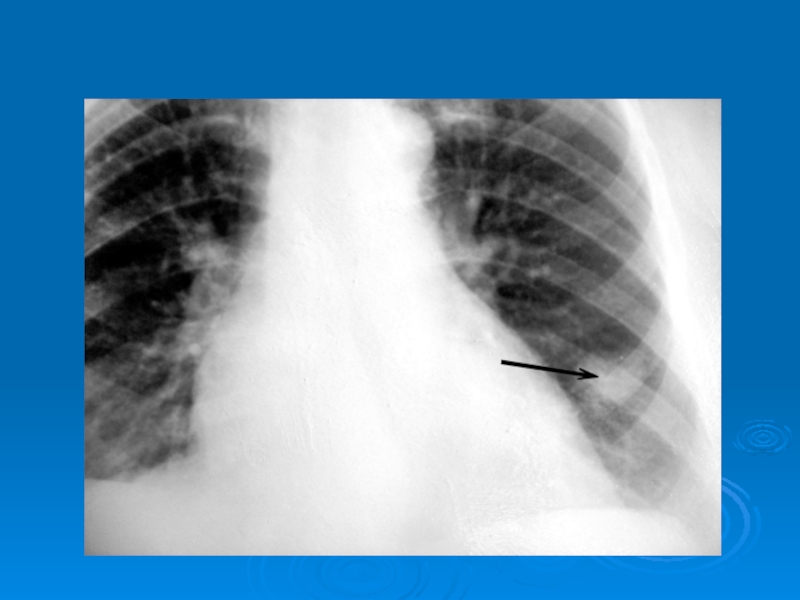

Слайд 41Отдельные очаги в лег. поле (опухоль в нижней доле левого

легкого)

Отдельные очаги в лег. поле (опухоль в нижней доле левого легкого)